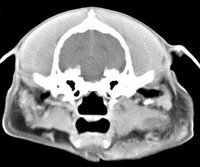

imágenes de TC en el perro | ||||||||||

ejemplo de imágenes de TC en el perro. Nótese la celulitis en la región parotídea izquierda | ||||||||||